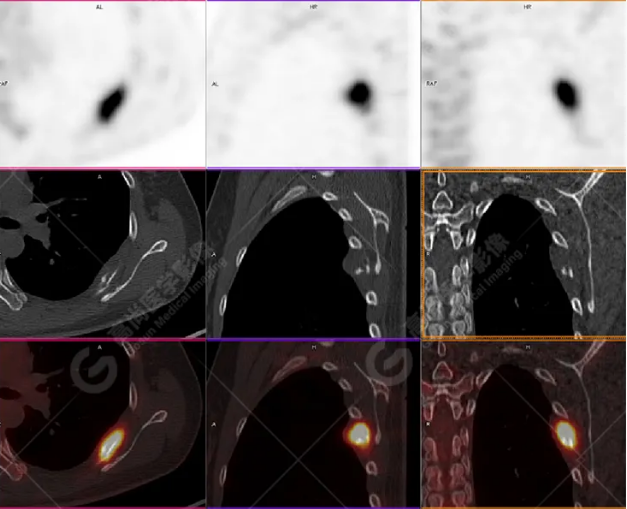

病史摘要:女性 36歲 因左后肋區(qū)疼痛1月余查體,無(wú)其他不適。PET/CT影像圖

左胸一后肋溶骨性骨質(zhì)破壞,周圍伴軟組織形成,F(xiàn)DG代謝增高,SUVmax為10.9。

找到引起骨痛病灶,病因:原發(fā)?轉(zhuǎn)移?感染?

最終診斷:宮頸癌伴肋骨單發(fā)骨轉(zhuǎn)移。